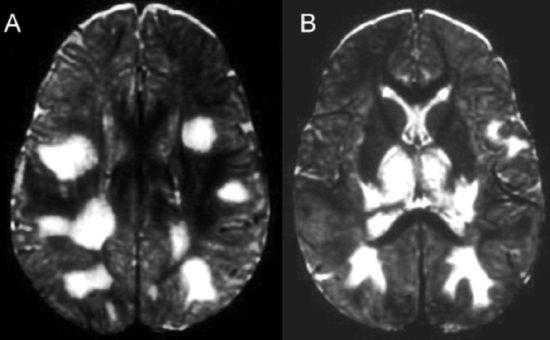

(а) Бесконтрастная КТ, аксиальный срез: у пациента 45 лет с лихорадкой и изменениями психического состояния в медиальном отделе правой височной доли определяется подозрительный участок слабого изменения плотности мозговой ткани.

(б) МРТ, Т2-ВИ, аксиальный срез: у того же пациента в медиальном отделе правой височной доли определяются изменения интенсивности сигнала. При исследовании СМЖ методом полимеразной цепной реакции (ПЦР) был выявлен ВПГ1. На ранних этапах течения герпетического энцефалита может сохраняться нормальная КТ-картина.

(а) Бесконтрастная КТ, аксиальный срез: у молодого взрослого с изменениями психического состояния в левой височной доле определяется отек и геморрагический компонент. Несмотря на раннее начало лечения ацикловиром данный пациент погиб. Смертность среди пациентов с герпетическим энцефалитом (ГЭ) варьирует от 50 до 70%.

(б) МРТ, Т1-ВИ, сагиттальный срез: у пациента через две недели после развития клинической картины герпетического энцефалита определяется потеря объема мозговой ткани височной доли. Кроме того, визуализируются линейные повторяющие ход извилин участки повышения интенсивности сигнала, которые расположены в структуре коры височной доли и характерные для подострого кортикального кровоизлияния.